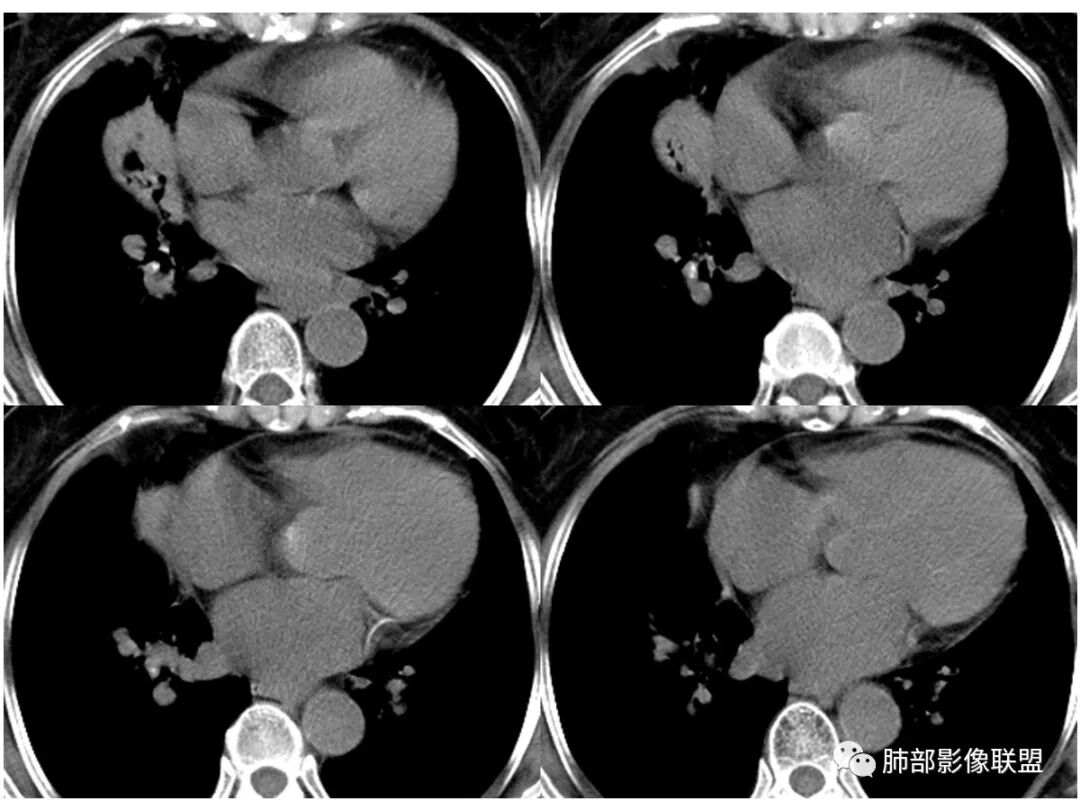

胸CT:右肺上叶实变内可见支气管充气征,近端支气管狭窄,远端扩张,周围可见毛玻璃影,右肺中叶支气管闭塞,并可见气道壁钙化,右肺中叶体积缩小,实变内可见空洞,并可见气液平面,空洞周围可见毛玻璃样影,右肺下叶支气管开口狭窄,右肺门淋巴结肿大。纵隔窗可见病灶与壁层胸膜间隙增宽,考虑良性病变-----感染性病变------TB?

右中叶支气管完全阻塞伴厚壁空洞,右上叶支气管不全阻塞伴大片GGN,右下部分GGN考虑腺鳞癌,结核待排。

老年女性,慢性病程,咳嗽伴白色粘液痰,无发热腹痛,糖尿病,白细胞及C反应蛋白不高,血沉快,铁蛋白高。胸部CT,右肺上叶大片状实变伴磨玻璃密度影,边界不清,边缘局部膨隆,叶裂弧形下坠,实变影宽基底与胸膜相贴;右肺下叶前基底段见类似病灶;右肺中叶不张并空洞形成,空洞内见气液平面;综合考虑右肺上叶及下叶肺炎型肺癌,右肺中叶结核。

这里是中叶的不张和空洞,有钙化,结核确实也不能排除

主病灶应该是粘腺腺癌,右中叶不张?,内空洞,壁光滑,考虑感染